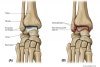

관절 연골은 소실, 관절연골은 협소화되고 연골하골의 경화, 낭포 형성이나 관절 주위의 골극 형성이 나타납니다.

측면에서는 거골 활차는 편평화, 정면에서는 둥그스름하게 되어, 내외과의 각도는 벌어집니다.